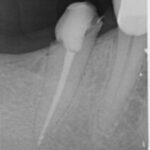

Zahn mit unvollständiger Wurzelfüllung und chronischer Entzündung an der Wurzelspitze

Nach medikamentösen Einlagen und vollständiger Wurzelfüllung – die Entzündung heilt ab